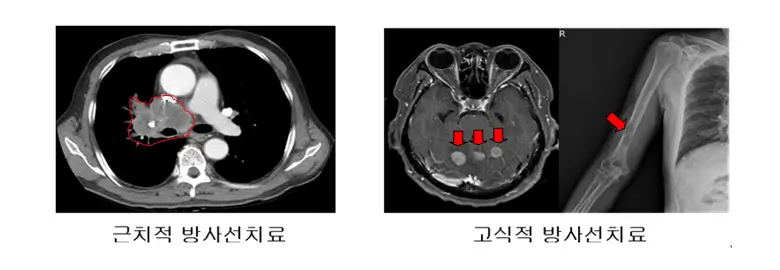

방사선치료

방사선치료는 고에너지의 방사선을 이용해 암세포를 죽이는 방법입니다. 주로 비소세포폐암의 초기 단계나 소세포폐암의 제한적 병기에 사용됩니다. 방사선치료는 국소 부위에 높은 에너지를 집중시켜 암세포의 성장을 억제하거나 파괴하는 데 효과적입니다.

방사선치료의 종류

방사선치료에는 외부 방사선치료와 내부 방사선치료가 있습니다. 외부 방사선치료는 몸 바깥에서 방사선을 쏘아 암을 치료하며, 내부 방사선치료는 방사성 물질을 암 조직 근처에 삽입하여 치료합니다.